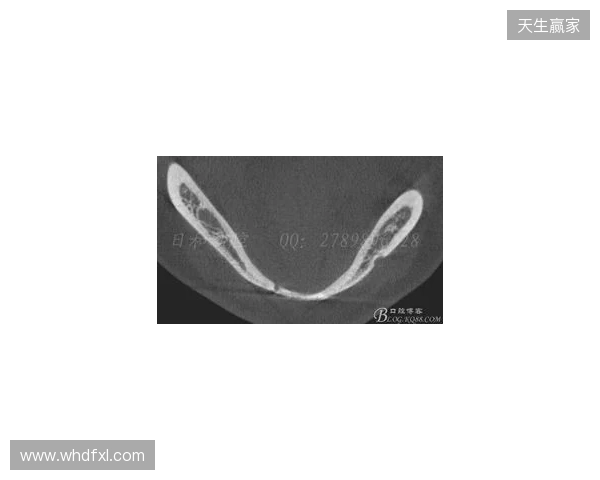

在2026赛季中超联赛首轮的比赛中,韦林顿·席尔瓦遭遇了严重的伤病,导致他上唇部受伤,并且出现了牙齿和牙槽骨的损伤。根据华西口腔医院的诊断,席尔瓦的伤情包括上唇部贯通伤、两颗牙齿半脱位以及上颌前牙区牙槽骨骨折。此事件不仅对球员本人构成了巨大的身体挑战,也给球队带来了不小的影响。伤病的发生让人揪心,球迷们纷纷为席尔瓦送上祝福,希望他能尽快康复,重返赛场。

根据医院的检查结果,韦林顿·席尔瓦的上唇部受伤程度较为严重,属于贯通伤,已经进行了清创缝合。这种类型的伤势不仅影响外观,还可zbo1919官网能对球员的饮食和发声造成影响。更为严重的是,他的上颌前牙区还出现了骨折,意味着席尔瓦在恢复期间将面临长时间的治疗和康复过程。

球员的第11和第21牙出现了半脱位的情况,这可能会导致他在恢复后需要进行进一步的牙科治疗,甚至有可能影响到他今后的职业生涯。医生表示,虽然通过手术和治疗可以恢复,但心理层面的恢复同样重要。